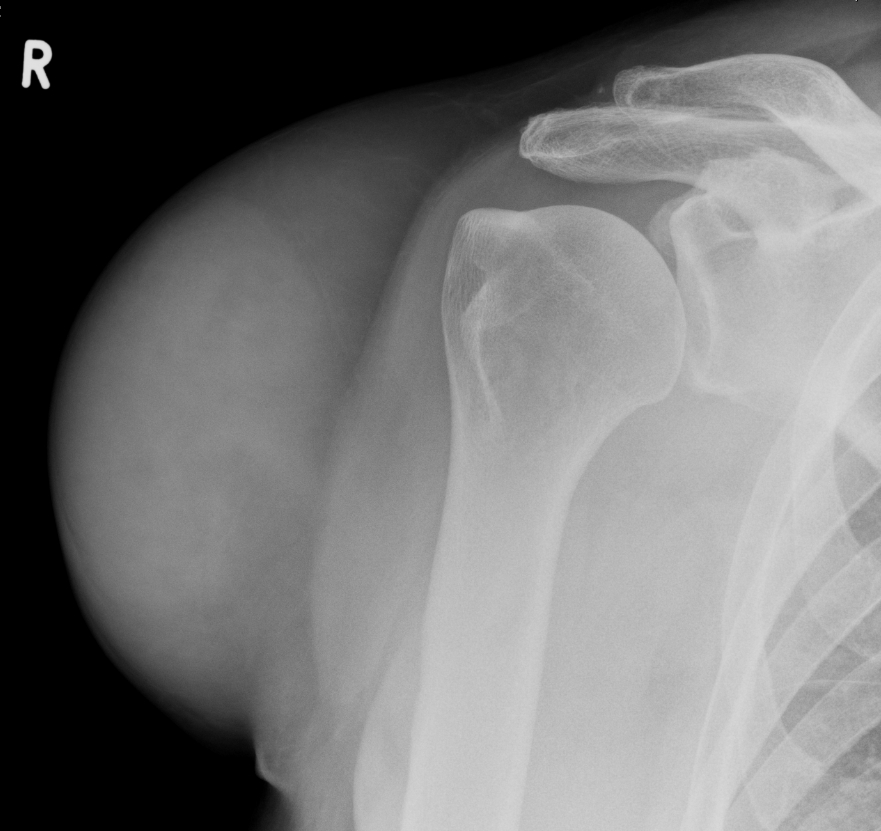

Рентгеновские снимки саркомы плечевого сустава